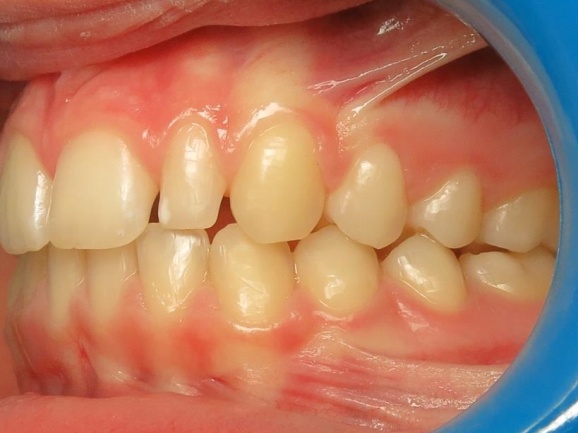

1 - Avant et après traitement

Un traitement orthopédique a permis d’optimiser la croissance des bases osseuses, offrant des conditions favorables à l’évolution de la dentition. Le traitement multiattaches a ensuite aligné les dents sur des structures squelettiques correctement développées.